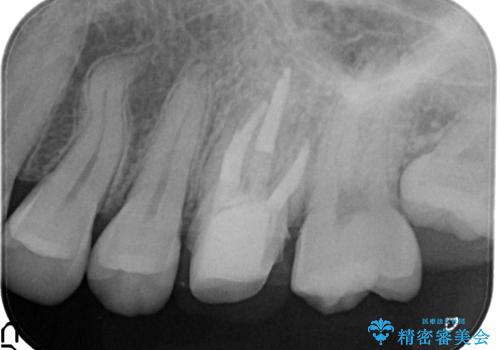

金属の奥歯 → 白い奥歯 根管治療からのやり直し

- 再根管治療→土台の築造 を行った上でのかぶせ物のやり替えをおこないました。

神経の無い歯のかぶせ物をやり替える際は、是非根管治療からしっかりやり直すことをおすすめします。